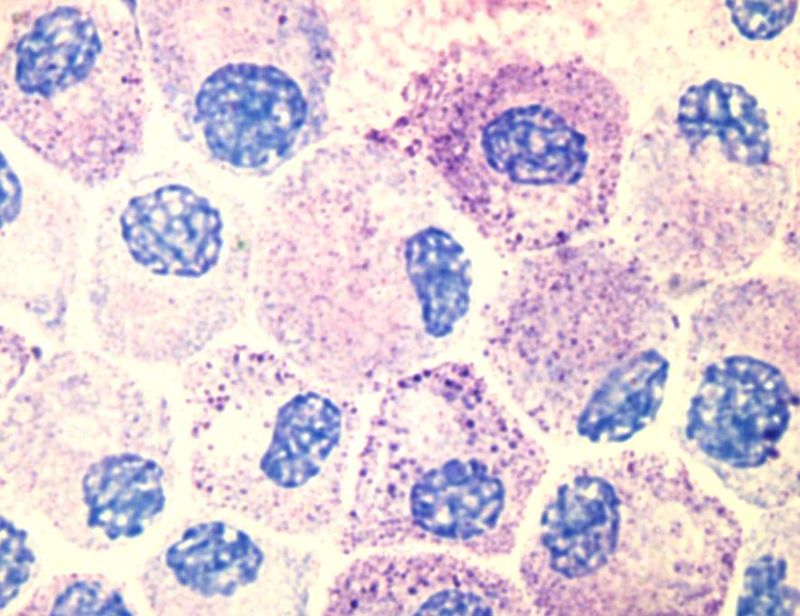

Ces cellules, décrites pour la première fois par Paul Ehrlich à la fin du XIX° siècle sous le nom de « cellules engraissées », sont synthétisées à partir de précurseurs de la lignée myéloïde produits dans la moelle osseuse. Elles sont au départ libérées dans le sang sous forme de cellules immatures, puis elles migrent vers les tissus lorsqu’elles se différencient. On les trouve en particulier dans le tissu conjonctif de la peau, la sous-muqueuse intestinale ou le tractus respiratoire, ainsi qu’à proximité des vaisseaux sanguins et des ganglions lymphatiques.

Une fois activés, les mastocytes libèrent dans leur environnement des granules préformés qu’ils contiennent dans leur cytoplasme. Ce processus porte le nom de dégranulation. Ces granules renferment des médiateurs immunoréactifs comme par exemple l’héparine ou l’histamine , dont la fonction est de favoriser le processus inflammatoire et d’éliminer le pathogène [2]. Les mastocytes sont également capables de produire d’autres substances telles que des médiateurs lipidiques, des cytokines (comme le TNFα) ou des chimiokines qui participent à la signalisation et à la communication cellulaire pour coordonner la réponse immunitaire innée et adaptative.